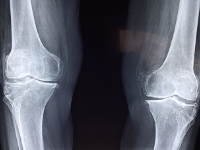

무릎 관절에 좋은 음식 무릎 관절 관리 방법 등 정보에 대해 알아보도록 하겠습니다. 무릎 관절은 우리 몸에서 가장 중요한 부위 중 하나입니다. 다리를 지탱하고, 움직임을 제공하는 기능을 수행합니다. 무릎 관절은 대개 체중과 운동에 의해 과부하가 걸리기 때문에, 연령과 상관없이 다양한 질환과 손상이 발생하기 쉽습니다. 무릎 관절 질환에는 퇴행성 관절염, 무릎 관절염, 슬관절 연골손상 등이 있습니다. 이러한 질환은 무릎 관절 통증, 붓기, 운동 제한 등의 증상을 유발합니다. 무릎 관절 건강을 유지하기 위해서는 적절한 운동, 올바른 식습관, 적절한 체중 유지, 적절한 자세 등이 필요합니다. 무릎 관절 질환의 예방과 관리를 위해서는 정기적인 건강 검진과 치료가 필요합니다.

무릎 관절염 원인

무릎 관절염의 원인은 여러 가지가 있지만, 가장 일반적인 원인은 연령, 체중, 유전적인 요인, 부상, 직업적 요인, 불규칙한 운동 등이 있습니다.

- 연령: 노화로 인해 무릎 관절 손상이 발생할 가능성이 높습니다. 연령이 들면서 연골이 더 얇아지고 윤활유 분비가 감소하게 되어 무릎 관절의 충격 흡수 기능이 감소합니다.

- 체중: 과체중은 무릎 관절에 대한 부담을 높이며, 무릎 관절의 염증을 일으키고 무릎 관절염 발병 위험을 높입니다.

- 유전적 요인: 유전적 요인도 무릎 관절염의 원인 중 하나입니다. 가족력이 있는 경우 무릎 관절염 발병 위험이 높아집니다.

- 부상: 무릎 관절 부상은 무릎 관절염의 발병 위험을 높입니다. 특히, 골절, 연골손상, 인대 손상 등이 무릎 관절염을 일으키는 원인이 될 수 있습니다.

- 직업적 요인: 직업적 요인으로 인해 무릎 관절 부담이 커지면 무릎 관절염 발병 위험이 높아집니다. 예를 들어, 무릎을 자주 굽히거나 일어설 필요가 있는 직업, 장시간 서 있는 직업 등이 그러합니다.

- 불규칙한 운동: 무릎 관절 부하를 지나치게 높이는 불규칙한 운동은 무릎 관절의 염증을 유발합니다.

무릎 관절염은 위와 같은 여러 요인들이 복합적으로 작용하여 발생할 수 있습니다. 따라서 무릎 관절염 예방 및 치료를 위해서는 건강한 식습관과 운동 습관을 유지하며, 무릎 관절에 대한 적절한 관리가 필요합니다.